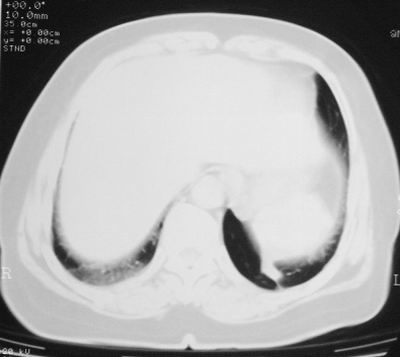

本次复查胸部ct

左下肺软组织块影,有分叶、毛刺、空泡及胸膜牵拉征,左下肺周围性肺癌。

左肺下叶周围型肺癌,支持!(软组织肿块+分叶+毛刺+空泡+胸膜凹陷征)

左下肺软组织密度影,可见分叶,边缘可见毛刺征,胸膜增厚,强烈要求左下肺周围型肺癌

左下肺后基底段实性肿块,周围有毛刺,病变周围有肺气肿,与降主动脉间有条带状影相连,病灶4年前查体发现,纵隔内未见肿大淋巴结。考虑.肺隔离症,建议增强扫描与周围型肺癌鉴别。